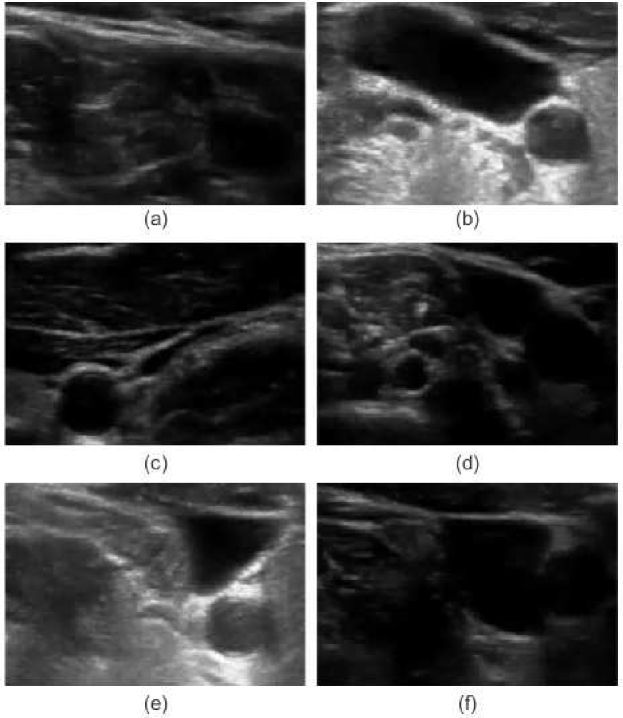

Determination of relative changes in circulating blood volume is important for a variety of acute and chronic medical conditions including hemorrhage from trauma, septic shock, dialysis and volume overload pertaining to congestive heart failure [1, 2, 3, 4, 5]. The estimation of absolute blood volume, while ideal, remains a significant challenge [6]. Recent studies suggest that non-invasive measures such as transverse ultrasound (cross-section area, CSA) of the internal jugular vein (IJV) can be used to detect and monitor relative changes in blood volume [7, 8]. As shown in Fig 1, the CSA of the IJV is dynamic with spatial and temporal variations that can correlate with relative changes in volume status. Short-term variability reflects a variety of factors including blood volume, proximity to the carotid artery, cardiac contractility, respiratory effort and local anatomy. Changes in parameters over the long-term can reflect relative changes in blood volume. Demonstration of short- and long-term CSA variability of a healthy patient sitting at different angles of inclination to simulate relative changes in circulating blood volume is shown in Fig. 2. Accurate segmentation and tracking of the rapidly changing IJV is fundamental to the use of ultrasound to estimate relative changes in blood volume.

In the case of broken edges, active contours fail to resolve the contours of intersecting objects resulting in leakage. An active shape model (ASM) using a statistical shape model can be used to address the above mentioned problem [33, 34]. Unfortunately, as per Fig. 1, the IJV assumes many different shapes and therefore, ASM is not applicable for the IJV segmentation. Other common approaches, such as Kalman filers, have been proposed for real-time vessel tracking in ultrasound imagery; however, similar to ASM, they require the geometry of the vessel [35].

This Section compares the tracking performance of the proposed Ad-PAC algorithm with the manual segmentation and other algorithms as per section V for two sample video as shown in Figs. 12 and 13, respectively. From both figures, it is evident that the proposed Ad-PAC algorithm outperforms the existing algorithms and produces results very close to the manual segmentation. Further supporting evidence that parameter adaption significantly improves the performance is evident in rows 3 and 4 row of Figs. 12 and 13. The segmented contour is not smooth without parameter adaptation (which is observed as spikes) suggesting that the weight given to the curvature energy term was not sufficiently large enough to compete with the other energy terms and consequently, dominated by them.

V-F Influence of IJV Shape